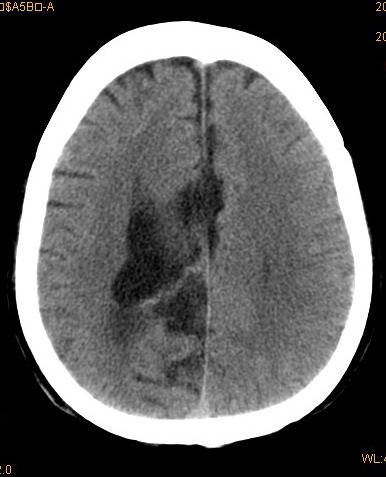

以下是引用卜一在2008-8-14 16:31:00的发言:[br]支持:巨脑回伴脑积水!另:胼胝体发育不良!

以下是引用随光逐影在2008-8-14 16:58:00的发言:[br]胼胝体发育不良;脑积水。

以下是引用同在2008-8-14 19:46:00的发言:[br]巨脑回伴积水,胼胝体发育不良.